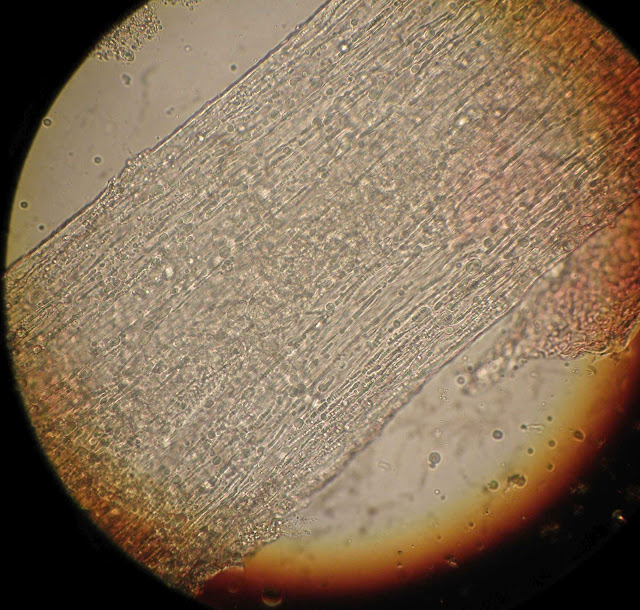

CABELO - EXAME MICROSCÓPICO

Exame microscópico  de um cabelo, ampliação 400x, entre lâmina e lamela com KOH.

Imagens capturadas antes de pressionar a lamela.